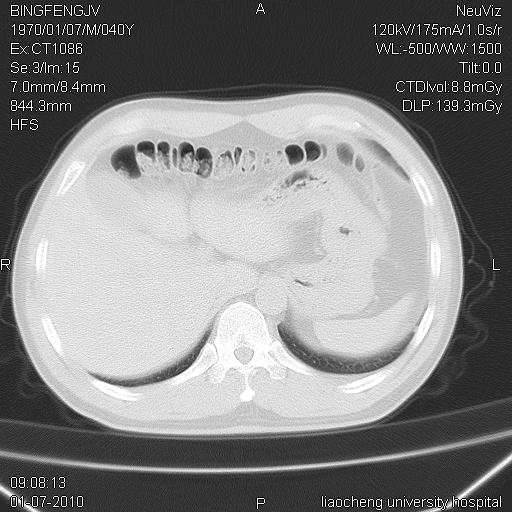

标题: CT23764B:男 40 肺部CT [打印本页]

标题: CT23764B:男 40 肺部CT

治疗2周后

考虑左肺上叶近胸膜下炎症并肺气囊形成。

炎症,大部吸收。